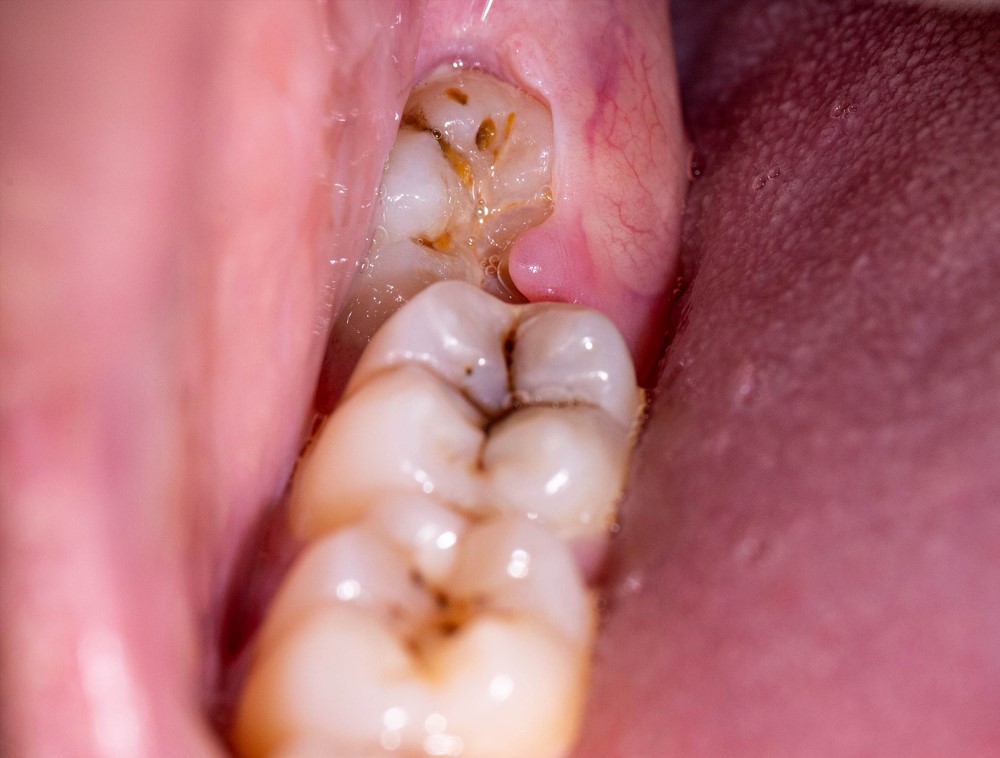

Lợi trùm có mủ là biến chứng thường gặp khi bệnh tái phát nhiều lần. Khi đó quanh bề mặt nướu sẽ xuất hiện các ổ mủ gây đau nhức, hôi miệng… Nếu không chữa trị kịp thời bệnh có thể dẫn đến áp xe nướu vô cùng nguy hiểm.

Vi khuẩn gây bệnh lợi trùm có thể di chuyển và gây sưng viêm, sâu răng, viêm nha chu…cho các răng bên cạnh. Điều này sẽ làm suy giảm chức năng ăn nhai, khả năng mất răng và vô cùng cao nếu không phát hiện và điều trị sớm